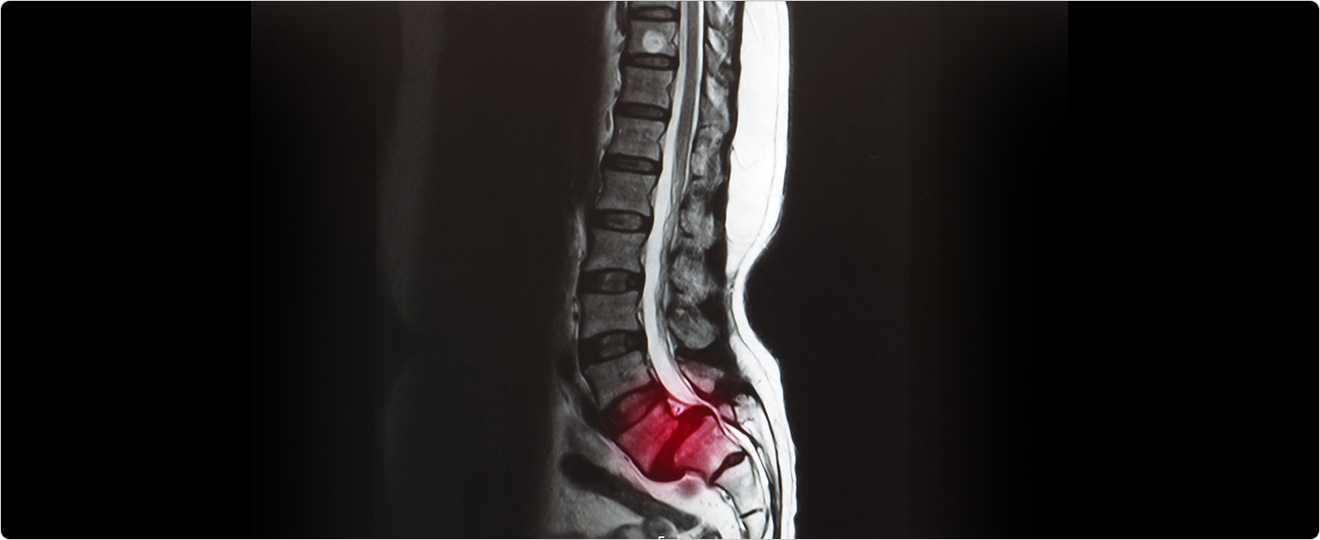

정상적인 척추의 정렬에서 벗어나, 하방의 척추체보다 상방의 척추체가 앞쪽으로 밀려있는 상태를 일컫습니다.

20대에서는 선천적인 척추의 협부 결손에 의한 협부형 척추전방전위증으로 발생하며, 40대 이후에서는 퇴행성 척추전방전위증이 발생합니다.

척추전방전위증이 발생한 부위에는 협착증이 동반되기 때문에, 환자분의 증상은 척추협착증과 동일한 허리 통증 및 엉덩이부근, 꼬리뼈 부위, 다리 방사통이 발생할 수 있습니다.